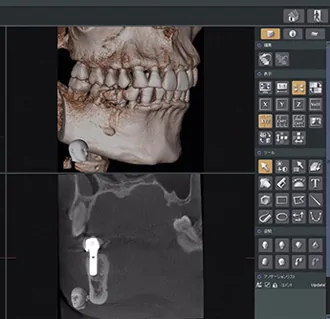

最新鋭の精密機器

歯科用CTによる正確かつ精密な把握

従来のレントゲンと異なり、患者様の骨の形状や、神経や血管の位置などインプラント施術に不可欠な様々な情報を、立体的に精密把握することができます。

骨の厚みや傾きなど、一人ひとり異なります。歯科用CTを使用することで術前から術中、術後もリアルタイムで口腔内の状況を正確に把握した施術ができるのです。

シミュレーションソフトによる事前予測の徹底

歯科用CTにて得られた情報を、シミュレーションソフトに取り込み、実際にインプラント埋入をどのように行うかを、コンピューター上でシミュレーションします。

ドクターの経験や勘は重要ではありますが、それに加え、データに基づいた事前シミュレーションの徹底により、人為的ミスを可能な限り排除したインプラント埋入を可能としています。